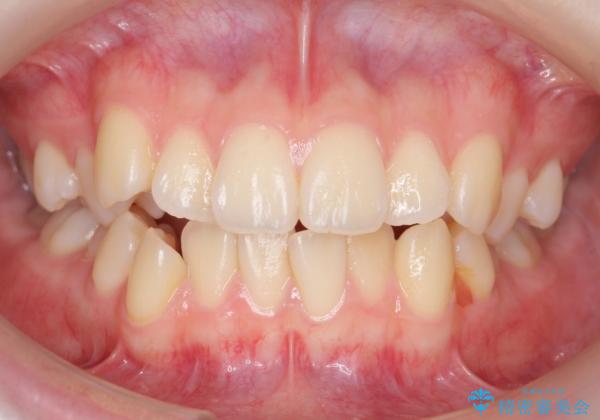

下の八重歯 歯を抜かずに インビザライン治療

- 歯並びのがたつきを主訴に来院。

抜歯してワイヤー矯正という選択肢も提案しましたが、マウスピース矯正で、歯を抜かずに並べてほしいとのことでした。

スペースを確保するために、歯をわずかに削る処置、奥歯を後ろに下げる処置(インプラント矯正)を行っています。

- 104.5万円(マウスピース矯正 93.5万円、矯正用スクリュー11万円)費用は治療当時の料金となります

途中患者様のご都合で治療を中断していたため、長くかかっていますが、実質2年程度で終わる内容でした。